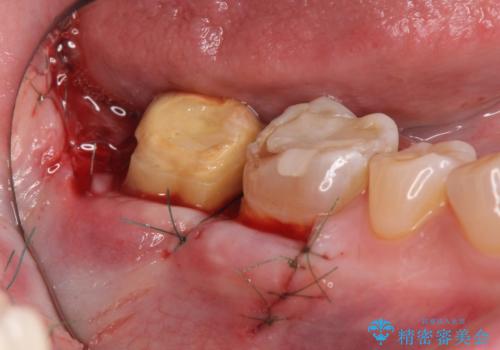

歯ぎしりによる異常に低い歯冠高径 歯周外科による解決

歯周外科を行い歯茎の位置を下げることで安定したクラウン製作ができる状態を目指します。

あまりにもクラウン高径が低いと、安定性が悪くなりセメントの溢出を招き虫歯の再発リスクを高めます。